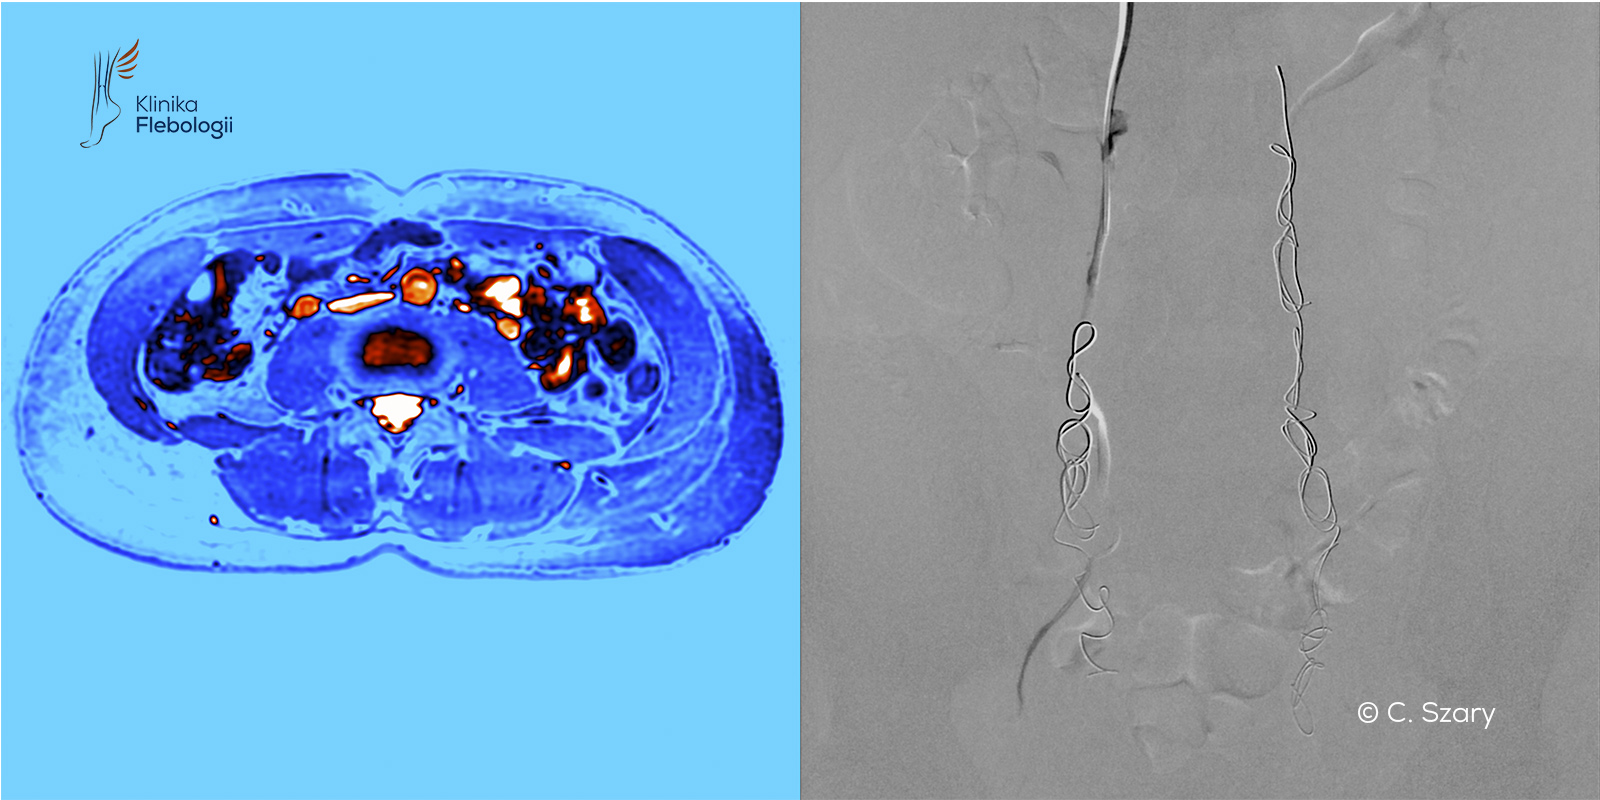

Decyzja i planowanie ewentualnego zabiegu poprzedzane są wykonaniem dokładniejszych badań obrazowych, takich jak wenografia MR lub TK. W zespole Kliniki Flebologii zajmują się tym specjalnie przeszkoleni radiolodzy: Michał Zawadzki i Cezary Szary.

W zależności od potrzeb specjaliści Kliniki Flebologii wykonują pełne spektrum badań obrazowych układu żylnego, tj.:

Badania oznaczone gwiazdką (*) wykonywane są przez naszych lekarzy radiologów w Szpitalu Medicover w Warszawie (dzielnica Wilanów). Badania wenograficzne w rezonansie magnetycznym (MRV) wykonywane są w Szpitalu Medicover oraz na miejscu we współpracy z Centrum Medycyny Sportowej w Warszawie (ul. Wawelska 5).

W tym celu wykorzystywany jest najnowszy wysokopolowy rezonans magnetyczny firmy Philips (siła pola magnetycznego 3 Tesle), który poza obrazowaniem układu żylnego w MR umożliwia diagnostykę najczęstszych chorób, imitujących objawy zespołu przekrwienia żylnego miednicy, takich jak: endometrioza, adenomioza macicy, zapalenie narządów miednicy mniejszej czy zapalenia jelita.

W pracowni hemodynamiki Szpitala Medicover stosujemy zdecydowanie najczęściej zabiegi małoinwazyjne przeprowadzane drogą wewnątrznaczyniową. Każdy zabieg wykonywany jest pod kontrolą sondy USG i cyfrowej aparatury angiograficznej (tworzony jest tzw. venogram).

czytaj więcejW dobie cyfryzacji sprzętu angiograficznego (bazującego na promieniach rtg), poprawie jakości obrazowania oraz wzrostu bezpieczeństwa środków kontrastowych flebografia diagnostyczna wykonywana na sali przeznaczonej zabiegów wewnątrznaczyniowych, stała się wyjątkowo precyzyjnym narzędziem w ocenie wielu stanów klinicznych związanych z chorobami układu żylnego.